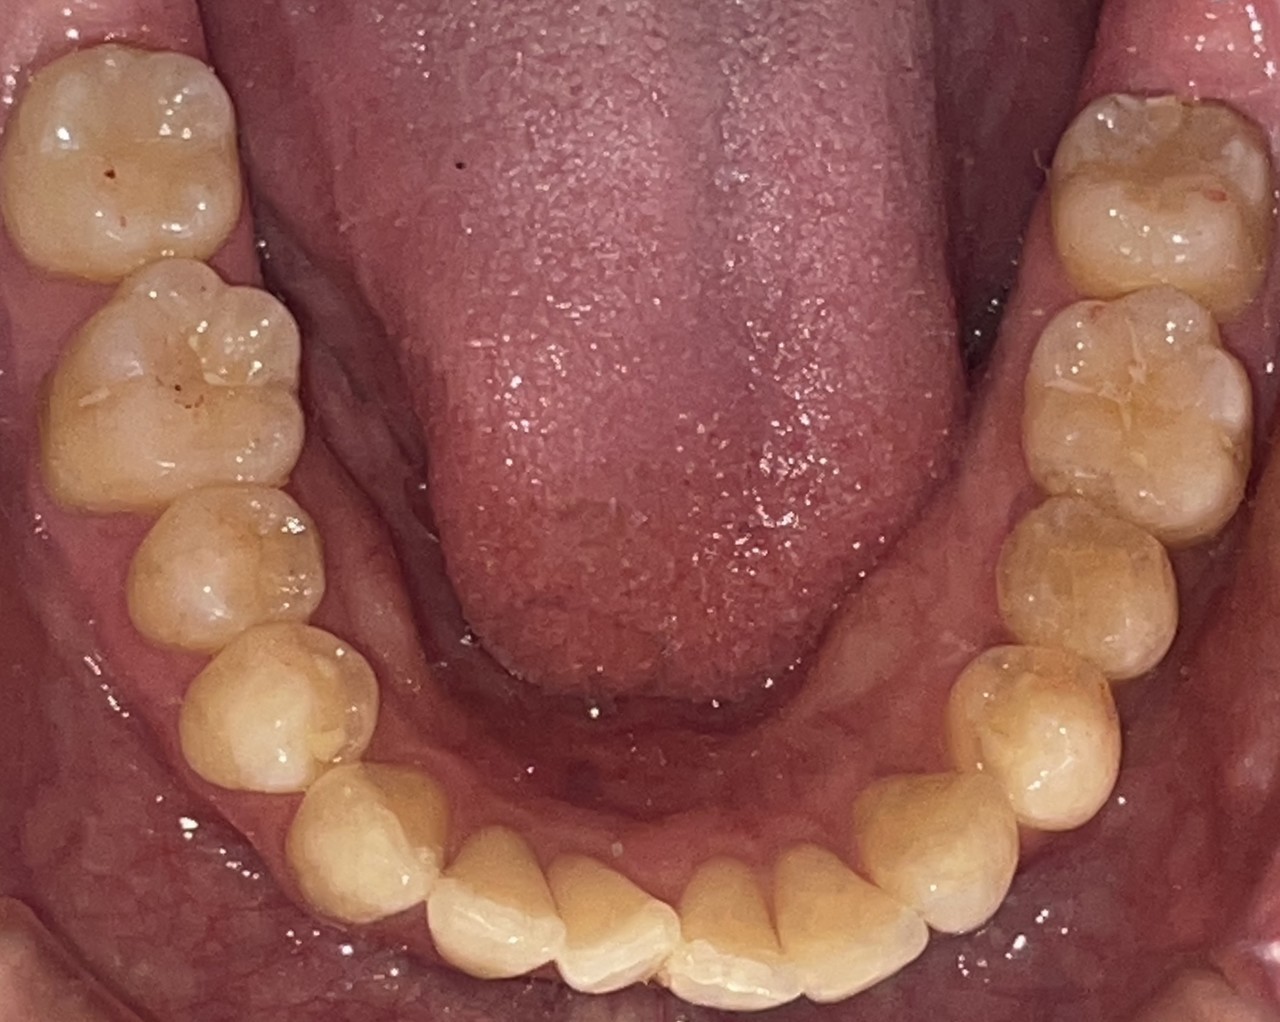

Before

After

矯正の種類 / invisalign GO

年齢・性別 / 30代女性

主訴  /  叢生、交叉咬合

治療期間 / 17ヶ月

費用 / 簡易検査 5,000円(税別) 精密検査 30,000円(税別)

両顎マウスピース 450,000円(税別) 両顎リテイナー料 60,000円(税別)

※マウスピース交換時別途調節料5,000円(税別)

副作用 / 口内炎・歯の移動に伴う痛み・知覚過敏 ※数日で収まる場合が多いです

リスク / 後戻り防止の為、夜のみマウスピースで保定を指示